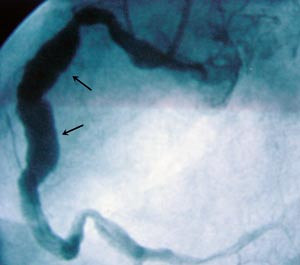

Pasienten ble henvist til regionsykehus med tanke på videre diagnostikk. Koronar angiografi viste ektatiske koronararterier uten signifikante stenoser (fig 3). MR av hjertet viste en solid rundaktig oppfylning på ca. 3,7 x 3,3 cm som lå like innenfor perikard, omringet av epikardialt fettvev. Største del av oppfylningen buket inn mot høyre atrium og hadde nær relasjon til tricuspidalklaffen og proksimale del av høyre ventrikkel. Den tentative diagnosen etter disse tilleggsundersøkelsene var hjertetumor eller aneurisme i en av koronararteriene.

Funn av patologiske strukturer i furen mellom høyre atrium og høyre ventrikkel ved ekkokardiografi bør gi mistanke om aneurisme i høyre koronararterie. Mistanken om at vår pasient kunne ha et slikt aneurisme, ble forsterket etter at koronarangiografi viste ektatiske koronarkar, siden aneurismer og ektasier ofte foreligger samtidig.

Ved torakotomi ble det funnet et stort trombosert aneurisme utgående fra høyre koronararterie (fig 4). Det ble gjort ekstirpasjon av selve aneurismet og koronar bypass av høyre koronararterie. Det ble også gjort lukking av en atrieseptumdefekt av secundum type.